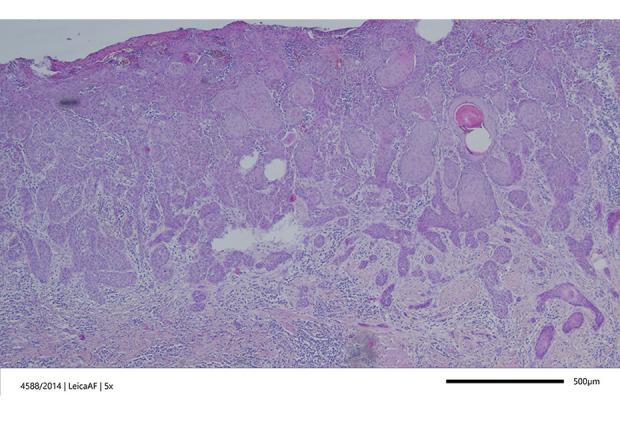

BACKGROUND Human Papilloma Virus (HPV)-associated Vulvar Squamous Cell Carcinomas (VSCC) present more frequently in young women than HPV- independent tumors. Due to its association with HPV infection, the incidence of vulvar cancer is increasing in young women; however, during pregnancy, it is still extremely rare. CASE REPORT We present the case of a 36-year-old pregnant woman at 23 weeks of pregnancy, diagnosed with HPV 16-associated VSCC, Federation of Gynecology and Obstetrics (FIGO) stage IB. Information on the coexistence of VSCC with pregnancy is unique, so it seems extremely important to disseminate it to develop the most effective treatment regimen. Additionally, making any decisions regarding therapeutic methods during pregnancy encounters great ethical problems. The size of the tumor was 0.5 cm with a depth of invasion 0.3 cm. The patient underwent therapy and gave birth by cesarean section at 38 weeks of pregnancy because of orthopedic indications. Surgical removal of the vulvar tumor was performed, including a margin of 1.5 cm of healthy tissue. Due to the patient's lack of consent, the sentinel node biopsy was not performed. No recurrence has been observed for 9 years. CONCLUSIONS The poorer prognosis of HPV-associated VSCC is independent of age and stage, with worse outcomes even in early-stage disease. For this reason, it is essential to sensitize clinicians to the possibility of such a diagnosis and to pay attention to the possibility of taking effective treatment during pregnancy, but safe for the fetus.

背景 人乳头瘤病毒(HPV)相关的外阴鳞状细胞癌(VSCC)在年轻女性中比HPV非依赖性肿瘤更常见。由于其与HPV感染相关,年轻女性外阴癌的发病率正在上升;然而,在怀孕期间,它仍然极为罕见。病例报告 我们报告一例36岁孕23周的孕妇,诊断为HPV 16相关的VSCC,国际妇产科联合会(FIGO)分期为IB期。VSCC与妊娠并存的信息很独特,因此传播该信息以制定最有效的治疗方案似乎极为重要。此外,在怀孕期间就治疗方法做出任何决定都会遇到很大的伦理问题。肿瘤大小为0.5 cm,浸润深度为0.3 cm。患者接受了治疗,并因矫形指征于孕38周行剖宫产分娩。对外阴肿瘤进行了手术切除,包括切除1.5 cm的健康组织边缘。由于患者不同意,未进行前哨淋巴结活检。9年来未观察到复发。结论 HPV相关VSCC的预后较差与年龄和分期无关,即使在疾病早期预后也较差。因此,必须提高临床医生对这种诊断可能性的认识,并关注在怀孕期间采取有效治疗但对胎儿安全的可能性。